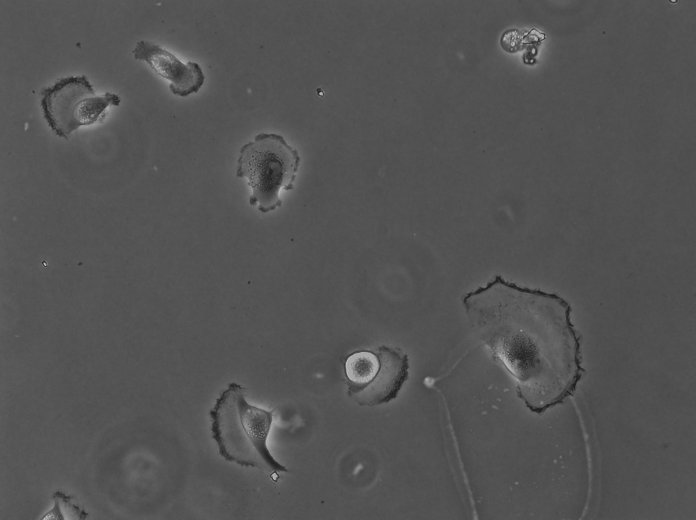

Thanks a lot for your response. About the dataset which i mean has the segmentation mask like below.

I used 30 image in training process but my jaccard Index is very low about 0.25. In your opinion how many annotated dataset i need to have good result in test set.

I put the dataset sample below and I did it for 20 epochs. after the 5th epoch, the dice and Jaccard index reduce significantly. yes, I cheeked the unet and got the accuracy of approximately 90 percent with this dataset. I thought that maybe your model is not robust in grayscale input image but after reading your paper, I figured out that you have used also grayscale images in your experiments. I use several Chanel is 3 for input dataset(each channel has the same input and merged with together in each steps. actually this dataset that i used is public dataset. i put input image with mask of dataset below.